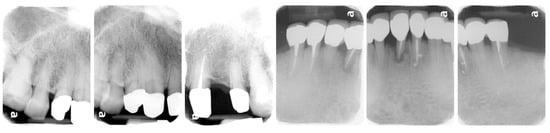

3. Results